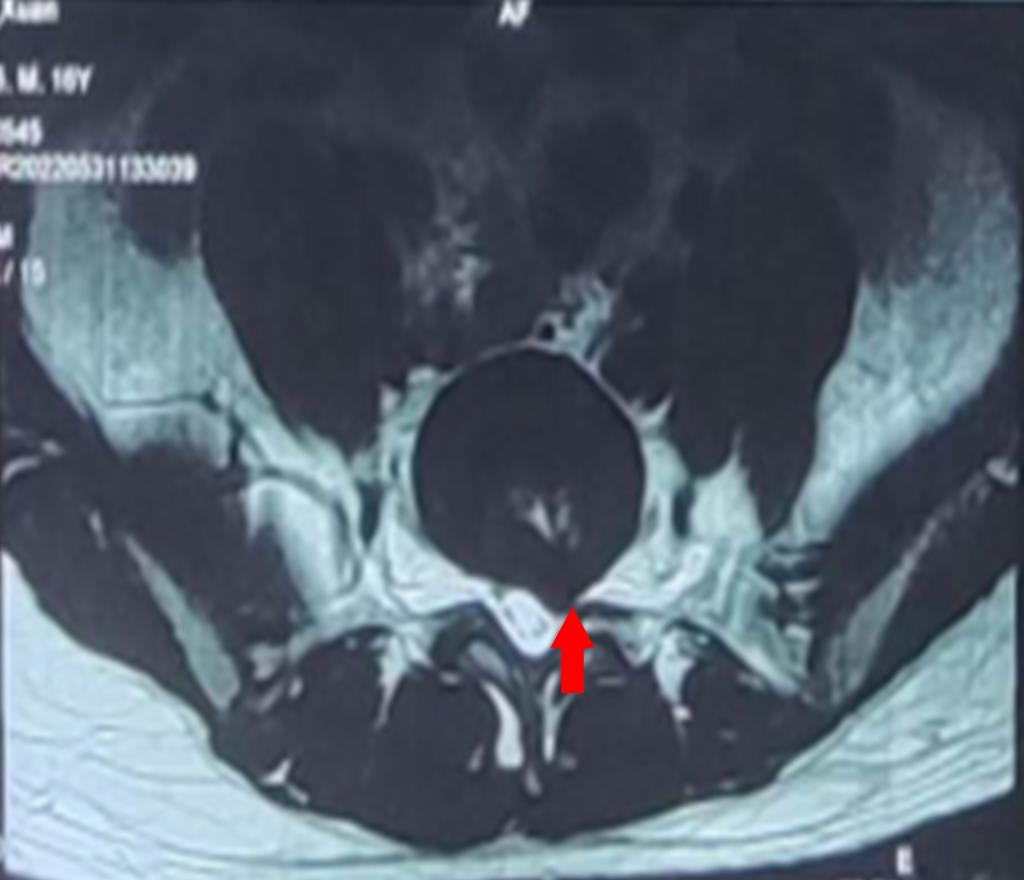

红色箭头:突出的L5/S1椎间盘

在家人的陪同下,小祁到家附近医院就诊,经腰部椎磁共振检测发现,小祁腰5/骶1椎间盘左后突出。

红色箭头:受压的S1神经根